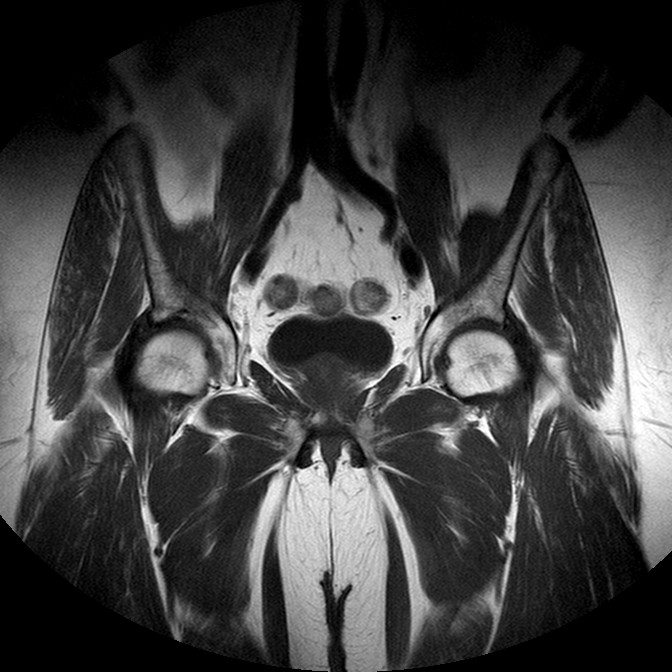

Esami: RMN BACINO

T1w TSE

Evidenti e simmetriche alterazioni osteofitosiche in regione coxo femorale con riduzione delle rime articolari. Degenerazione completa del cercine glenoideo. Non attuali segni di versamento articolare. Non segni di edema osseo che escludono attuale algodistrofia od osteonecrosi. Lieve e simmetrica riduzione del trofismo della muscolatura glutea.